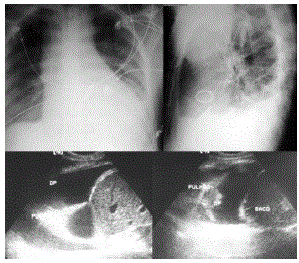

Paciente do sexo masculino, 68 anos, com quadro de cansaço e dispneia importantes realizou exames de tórax no serviço de imagem.

Baseado nas imagens disponibilizadas, qual o seu diagnóstico e qual a prótese valvar identificada?